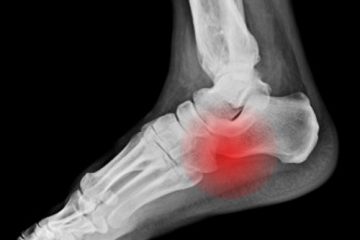

Κάταγμα Κάταγμα είναι η κάκωση του οστού κατά την οποία προκαλείται διακοπή της συνέχειάς του, όταν σπάζει δηλαδή ή ραγίζει σε κάποιο σημείο του. Το κάταγμα είναι συνήθως αποτέλεσμα τραυματισμού. Μπορεί όμως να είναι αποτέλεσμα ασθένειας του οστού που οδηγεί στην αποδυνάμωσή του όπως π.χ. η οστεοπόρωση (οστεοπορωτικά κατάγματα) ΜΟΡΦΕΣ Read more…